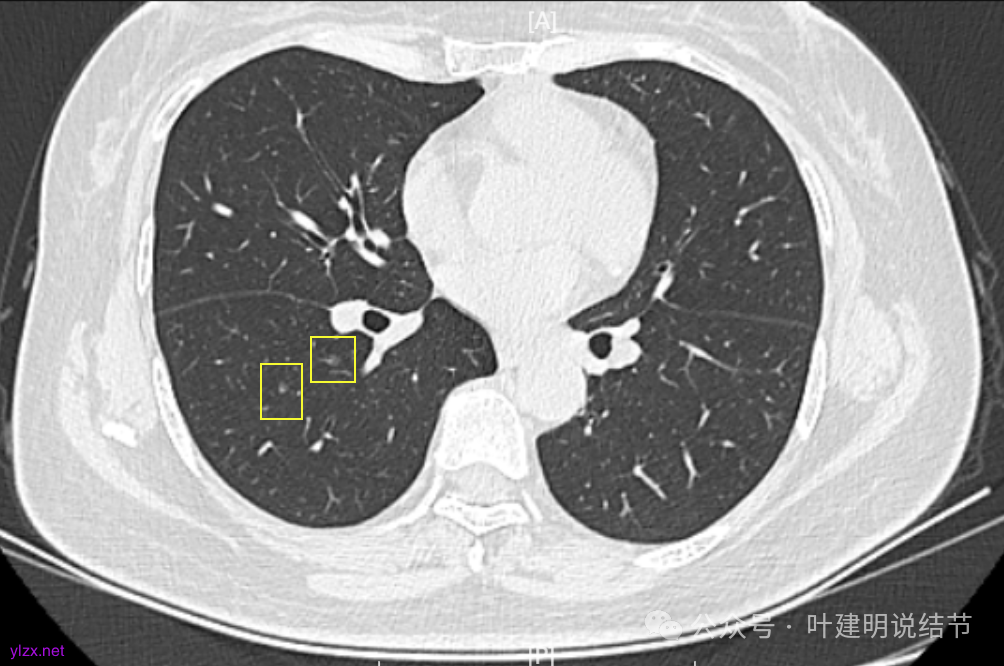

我们发现其实各病灶与三年前比说不上显著进展。

两肺多发磨玻璃结节,主病灶混合密度且有小血管进入,表面不平有毛刺,考虑微浸润性腺癌或浸润性腺癌可能性大,其余部分考虑原位癌或微浸润性腺癌,部分考虑肺泡上皮增生或不典型增生可能。总体上对比2022年说不上太明显的进展。但对于是否手术来讲,我仍倾向当年的意见,左侧的可以考虑近期亚肺叶(个人倾向楔切)切除,右侧的先随访,以后有进展并风险增加再考虑干预处理。因为要拉长两次手术的间隔,这样对机体的创伤与恢复更加有利一些。若定要仍不开刀,则建议要4-6个月复查,不过个人不太主张过于保守随访,对于像主病灶这种有少许实性成分的,不能保证肯定安全。意见供参考!